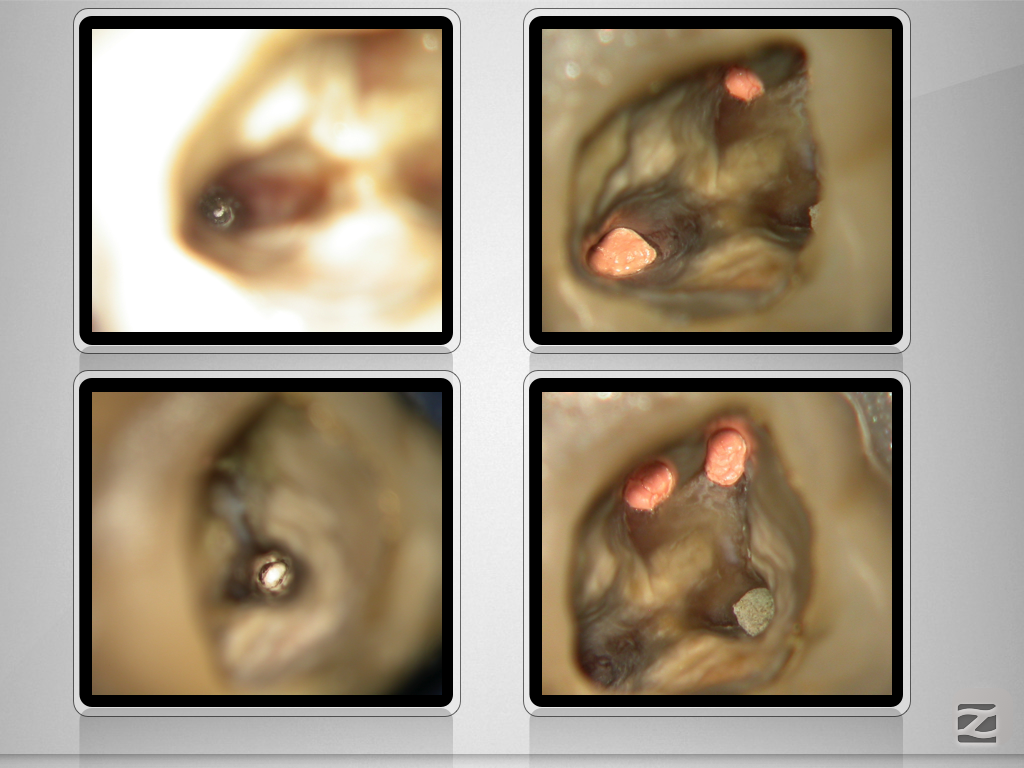

16D.007

1024 × 768

Von allem etwas …